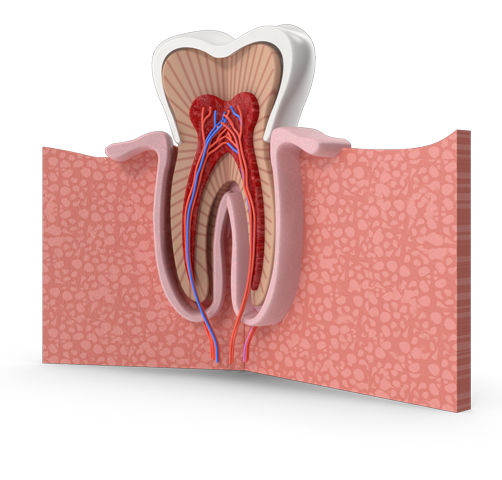

Η περιοδοντολογία ασχολείται με τη διάγνωση και τη θεραπεία των νόσων των ούλων και των υποστηρικτικών ιστών των δοντιών. Η υγεία των ούλων είναι θεμελιώδης για την υγεία όλου του στόματος, καθώς η φλεγμονή των ούλων μπορεί να οδηγήσει σε σοβαρές επιπλοκές, όπως απώλεια δοντιών και συστηματικές παθήσεις.